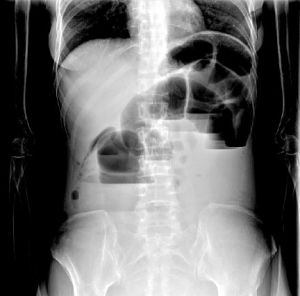

液氣平面是指腸內積存液體、氣體。腸炎、腹瀉、腸激惹時可見多發小液氣平面,此點臨床上常見誤診為腸梗阻,尤其腹瀉一段時間時,停止腹瀉時,放射科只要看見液氣平面,不管大小均提示符合腸梗阻,此點是其職責,故應結合病史、體徵,確定是否存在梗阻,但如出現較寬大液氣平面或階梯狀分布者應考慮存在梗阻,尤其可聞及金屬音腸鳴時。